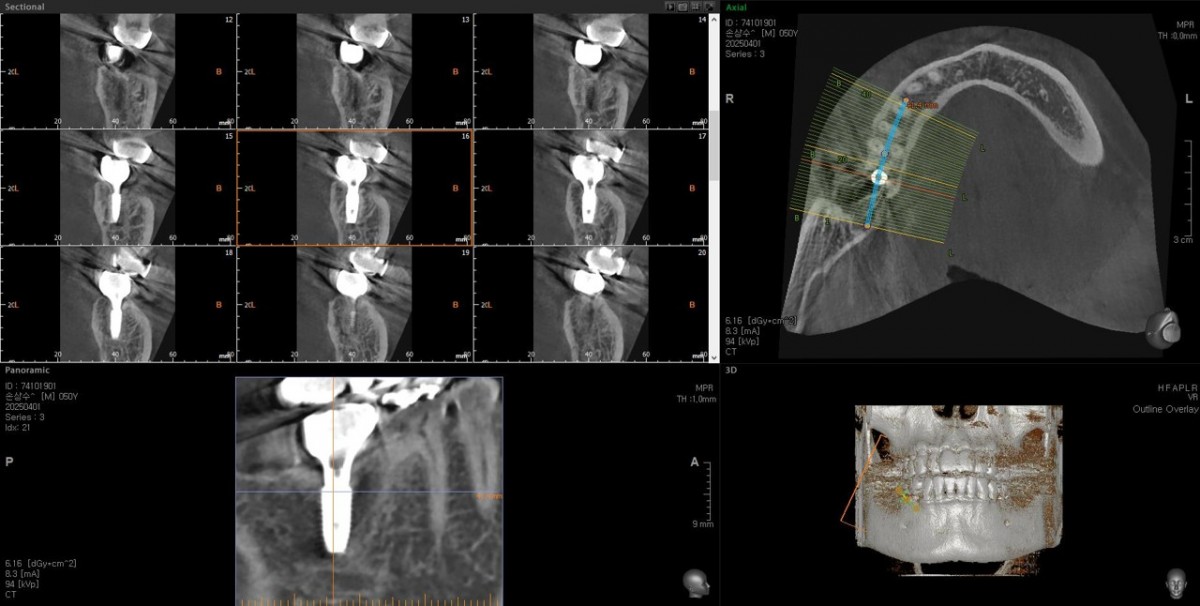

Single implant (staged) Arum NB1, f/u

A 47-year-old male patient had a crown with an ill-fitting margin and crack-tooth syndrome in the lower 2nd molar. No systemic issue.